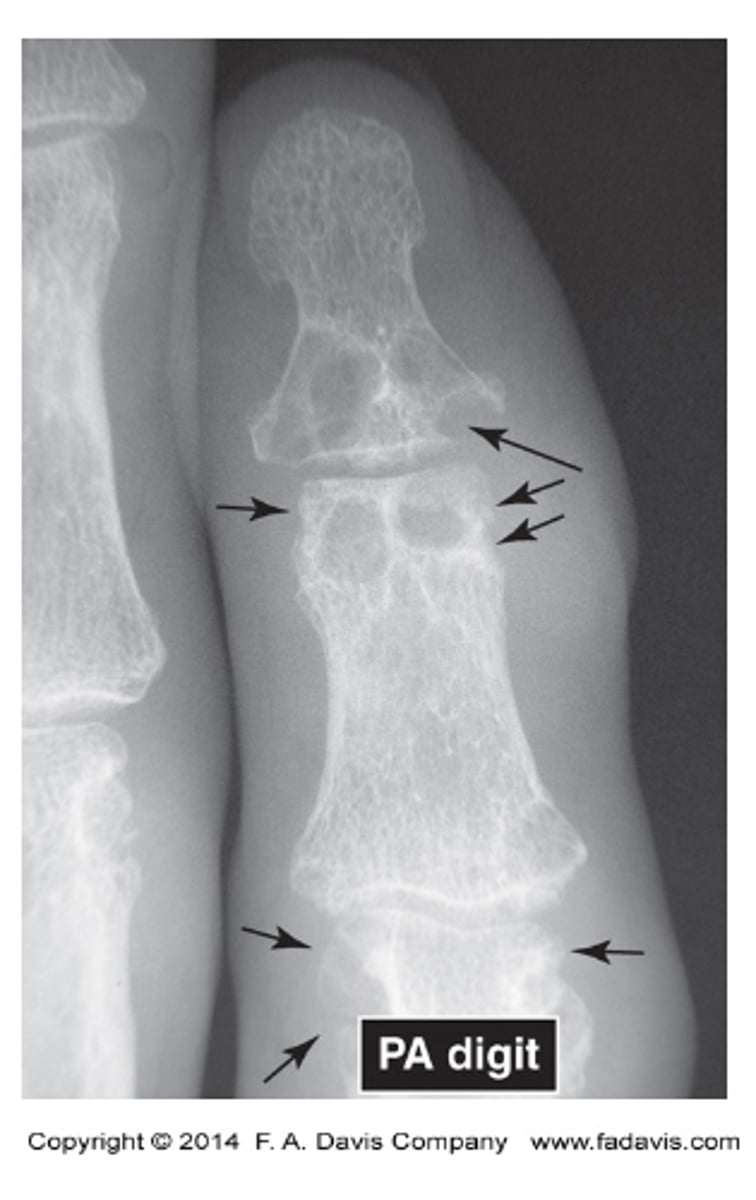

what does gout look like

increased radiolucency

will got be more radiodense or radiolucent

Subchondral bone erosions